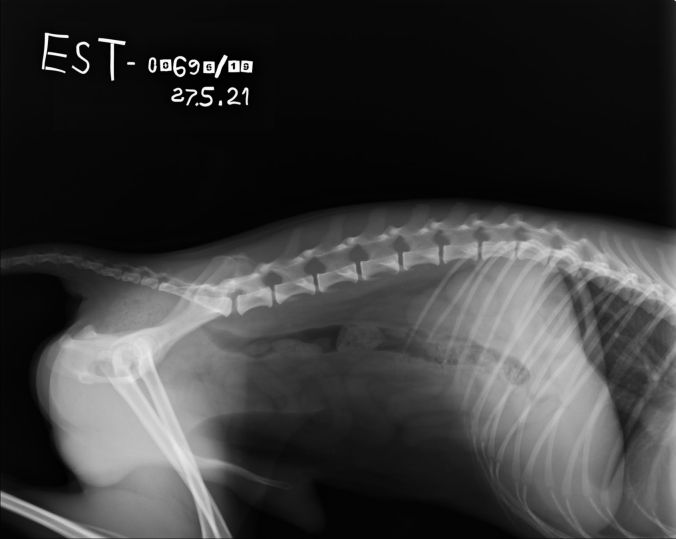

Spondyloosi

Spondylosis deformans eli spondyloosi on selkärangan rappeumasairaus, jossa selkänikamien rajoille muodostuu luupiikkejä ja/tai -siltoja. Spondyloosia kehittyy usein normaalistikin ikääntymisen myötä, mutta tietyillä roduilla rappeumaa todetaan jo nuorilla koirilla.

Silloittumat ovat yleisimpiä rintarangan loppuosassa ja lannerangan sekä ristiselän alueella, joten rinta- ja lannerangasta otetut sivukuvat ovat riittäviä kartoituskuvaamisessa.

Virallisen tutkimuksen alaikäraja on 24kk